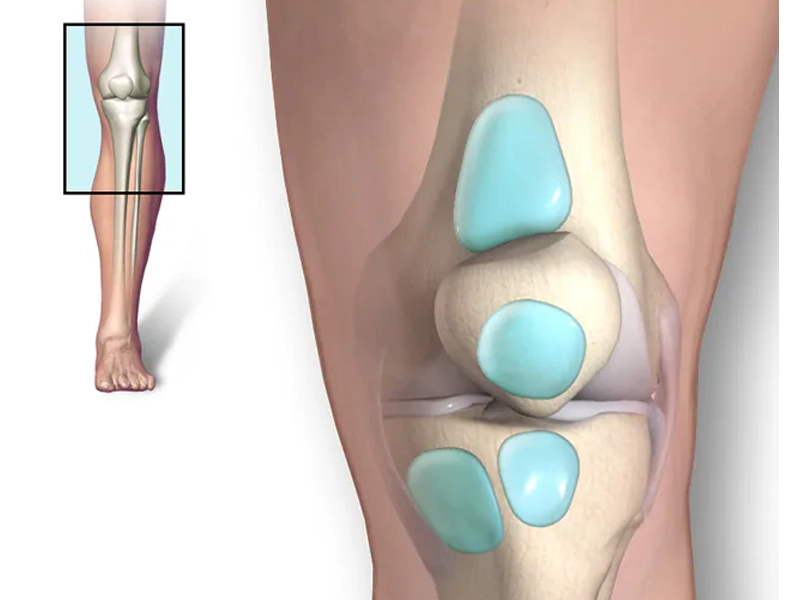

منیسک زانو دو غضروف نیم‌دایره‌ای‌شکل در داخل مفصل زانو هستند که مانند کمک‌فنر، وظیفه جذب فشار، پایداری و توزیع وزن در زانو را بر عهده دارند. پارگی منیسک یکی از شایع‌ترین آسیب‌های مفصل زانوست که می‌تواند به‌دلیل ضربه، چرخش ناگهانی یا فرسایش ناشی از افزایش سن ایجاد شود. پارگی منیسک زانو می‌تواند به‌صورت خفیف، متوسط […]